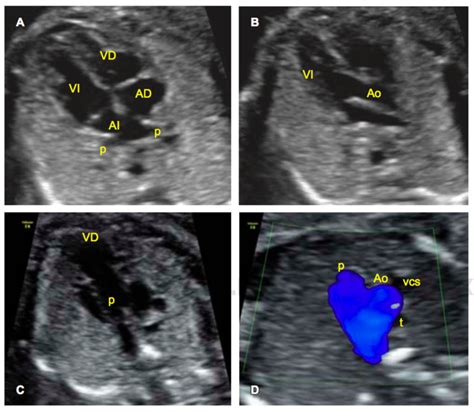

- Corazón: Se determina su orientación, se evalúa el corte de cuatro cámaras, las válvulas y tabiques, la salida de los grandes vasos y el retorno venoso. La ecografía Doppler color es opcional para este estudio. Las anomalías cardíacas son de las más difíciles de diagnosticar.